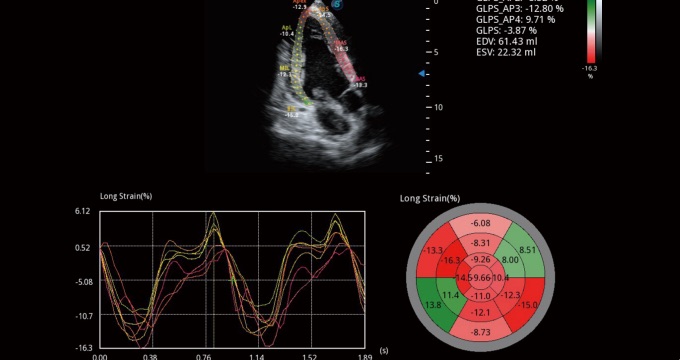

通過(guò)心肌識(shí)別技術(shù)和二維斑點(diǎn)追蹤技術(shù)相結(jié)合,計(jì)算心肌各節(jié)段的應(yīng)變應(yīng)變率、速度、位移并以曲線(xiàn)圖顯示,實(shí)現(xiàn)整體或者局部心肌定量分析。同時(shí)可呈現(xiàn)牛眼圖直觀和準(zhǔn)確診斷心肌的運(yùn)動(dòng)情況。